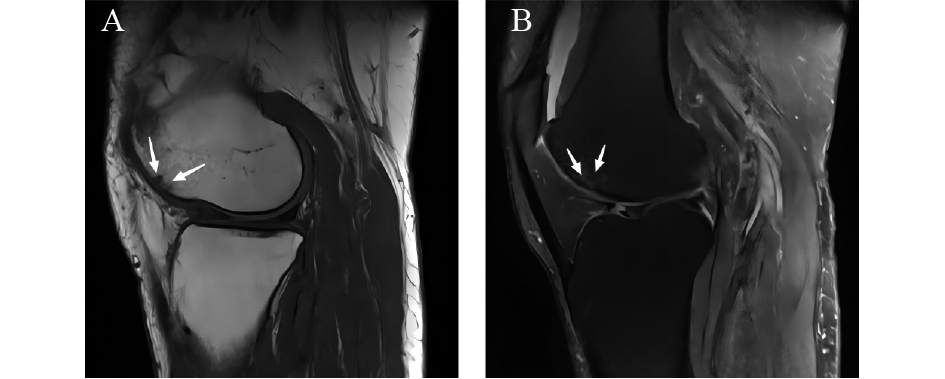

Osteoarthritis (OA) is a degenerative bone disease associated with aging. The rising global aging population has led to a surge in OA cases, thereby imposing a significant socioeconomic burden. Researchers have been keenly investigating the mechanisms underlying OA. Previous studies have suggested that the disease starts with synovial inflammation and hyperplasia, advancing toward cartilage degradation. Ultimately, subchondral-bone collapse, sclerosis, and osteophyte formation occur. This progression is deemed as “top to bottom.” However, recent research is challenging this perspective by indicating that initial changes occur in subchondral bone, precipitating cartilage breakdown. In this review, we elucidate the epidemiology of OA and present an in-depth overview of the subchondral bone’s physiological state, functions, and the varied pathological shifts during OA progression. We also introduce the role of multifunctional signal pathways (including osteoprotegerin (OPG)/receptor activator of nuclear factor-kappa B ligand (RANKL)/receptor activator of nuclear factor-kappa B (RANK), and chemokine (CXC motif) ligand 12 (CXCL12)/CXC motif chemokine receptor 4 (CXCR4)) in the pathology of subchondral bone and their role in the “bottom-up” progression of OA. Using vivid pattern maps and clinical images, this review highlights the crucial role of subchondral bone in driving OA progression, illuminating its interplay with the condition.